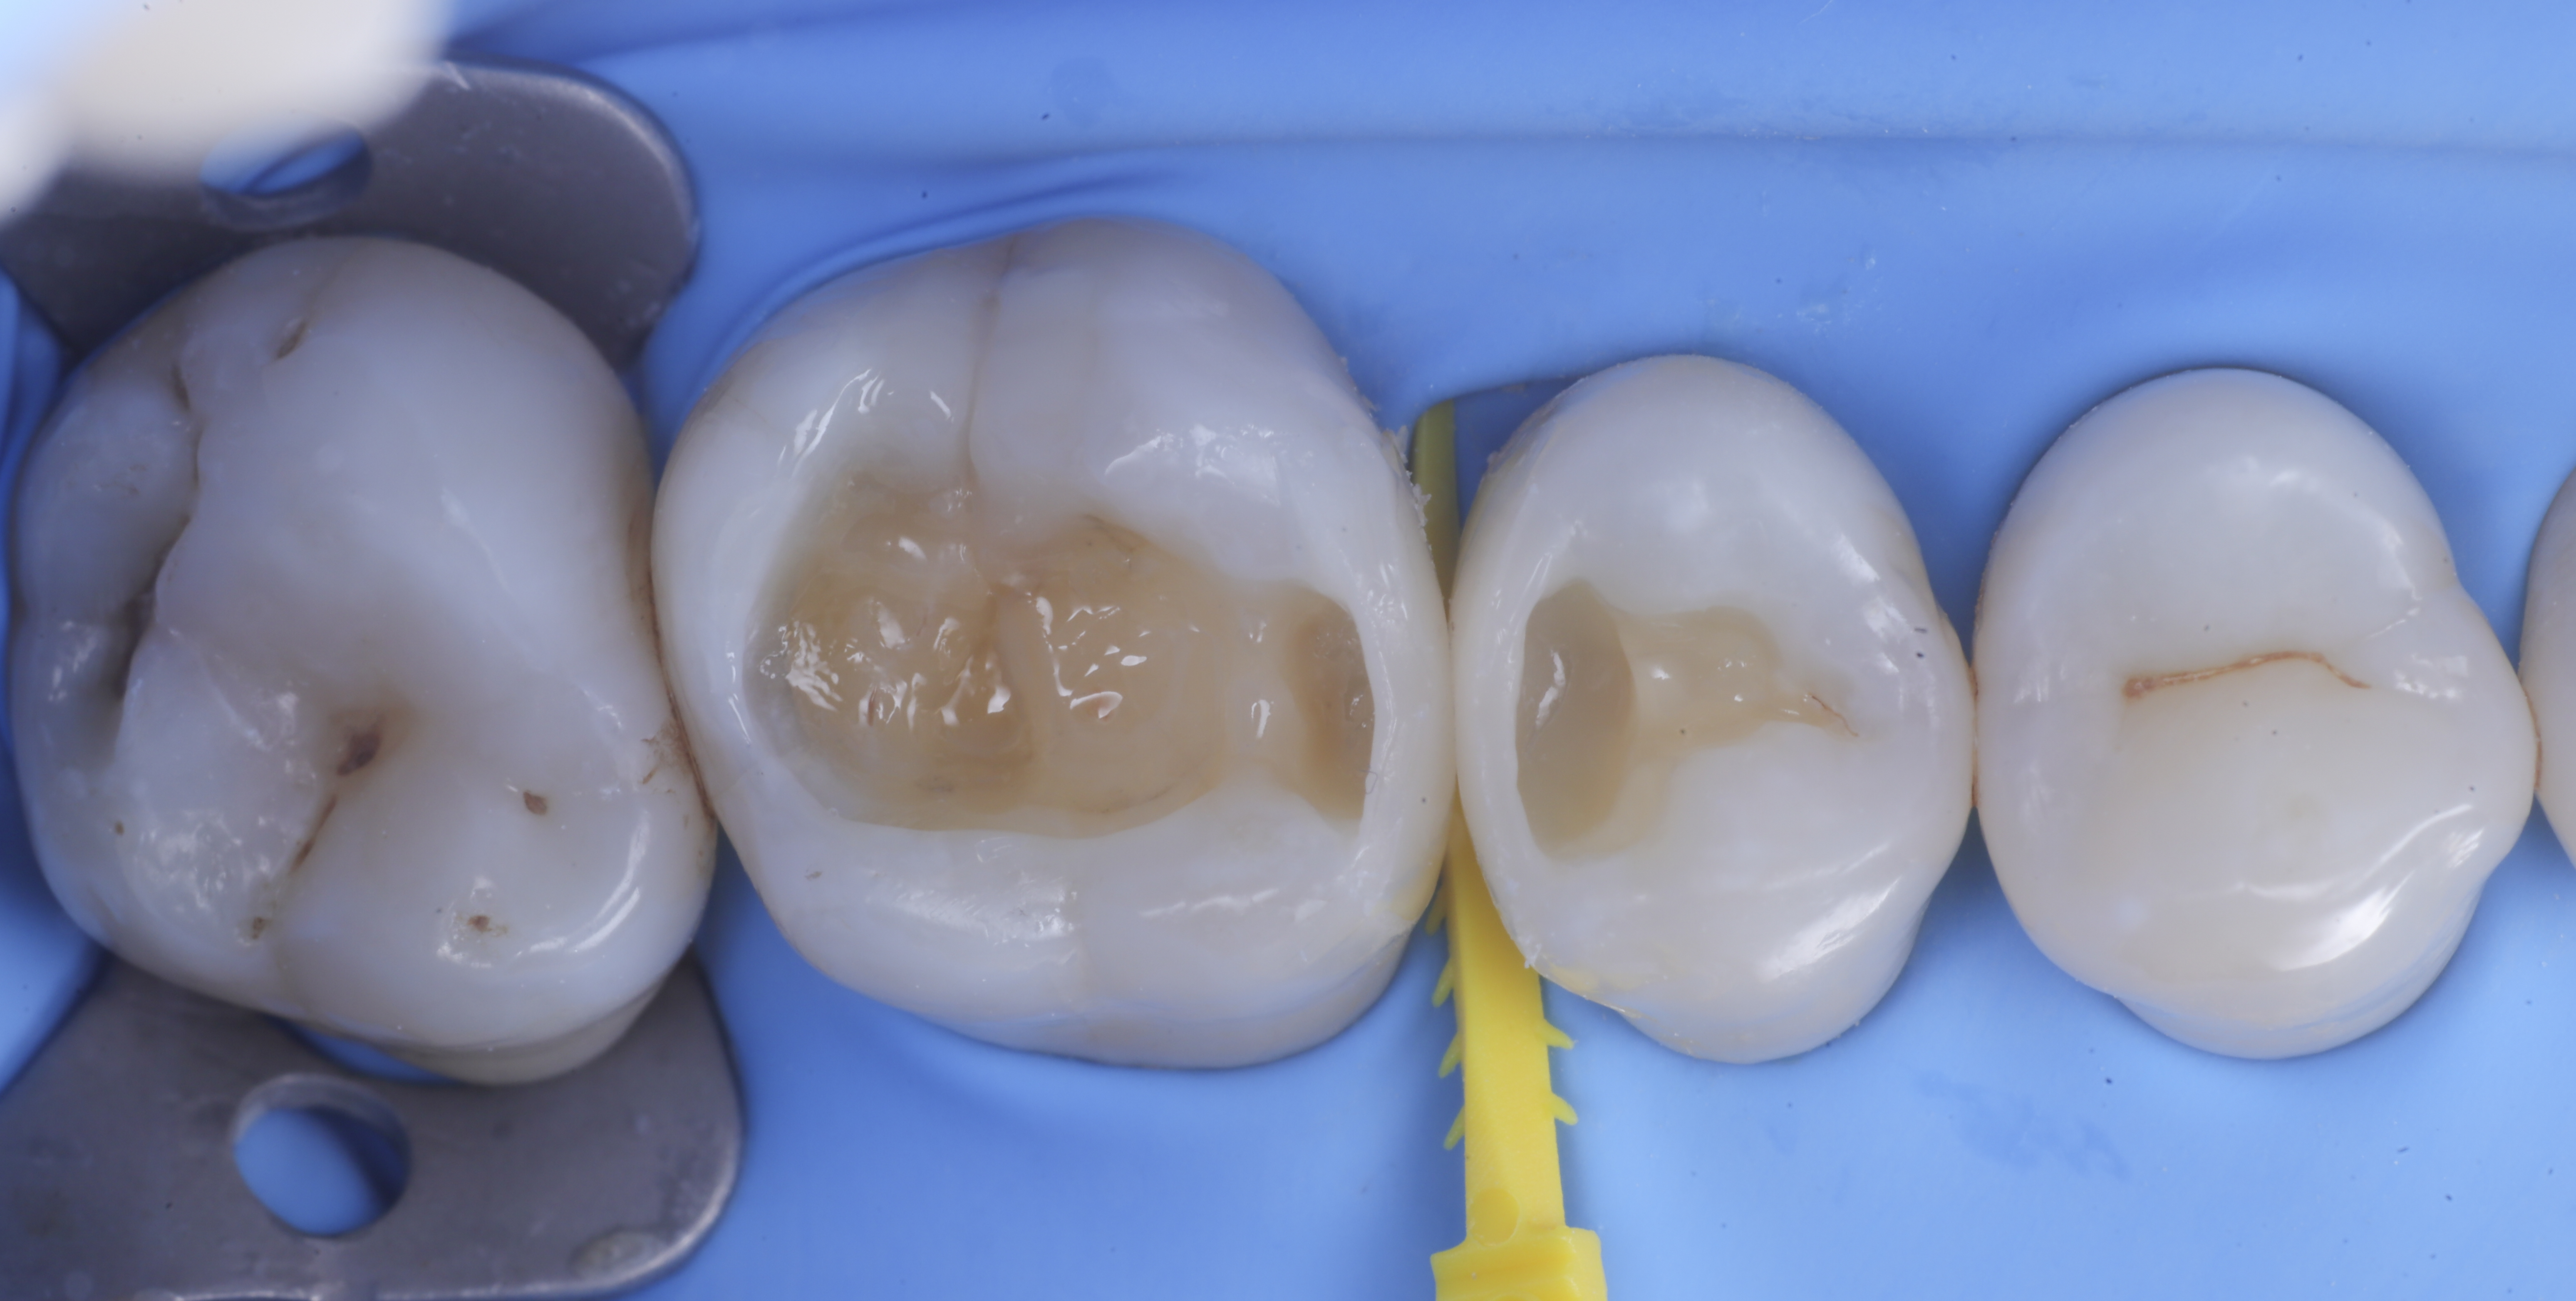

foto 4 Aspetto della chiusura cervicale e sulle pareti assiali dato dalla prima matrice

foto 5 Aspetto della chiusura cervicale e sulle pareti assiali della seconda matrice